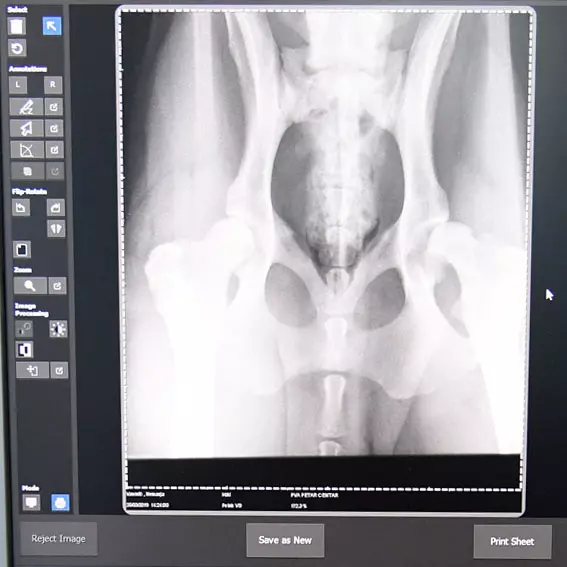

Nalazimo se na adresi Petra Drapšina 70. Radimo rendgensku dijagnostiku kod životinja u maloj praksi i vršimo izdavanje sertifikata za kukove i laktove pasa.

Među mnogim delatnostima koje veterinarska stanica "Doki-Vet" obavlja, izdvajamo rendgensko dijagnostikovanje kod životinja a takođe nudimo sve ostale usluge:

Mi imamo najpreciznije rendgensk dijeagnostike kod životinja, jer pored velike stručnosti koju posedujemo, koristimo i najsavremeniju opremu.

Rendgensko dijagnostikovanje kod životinja u Čoki, samo kod nas!